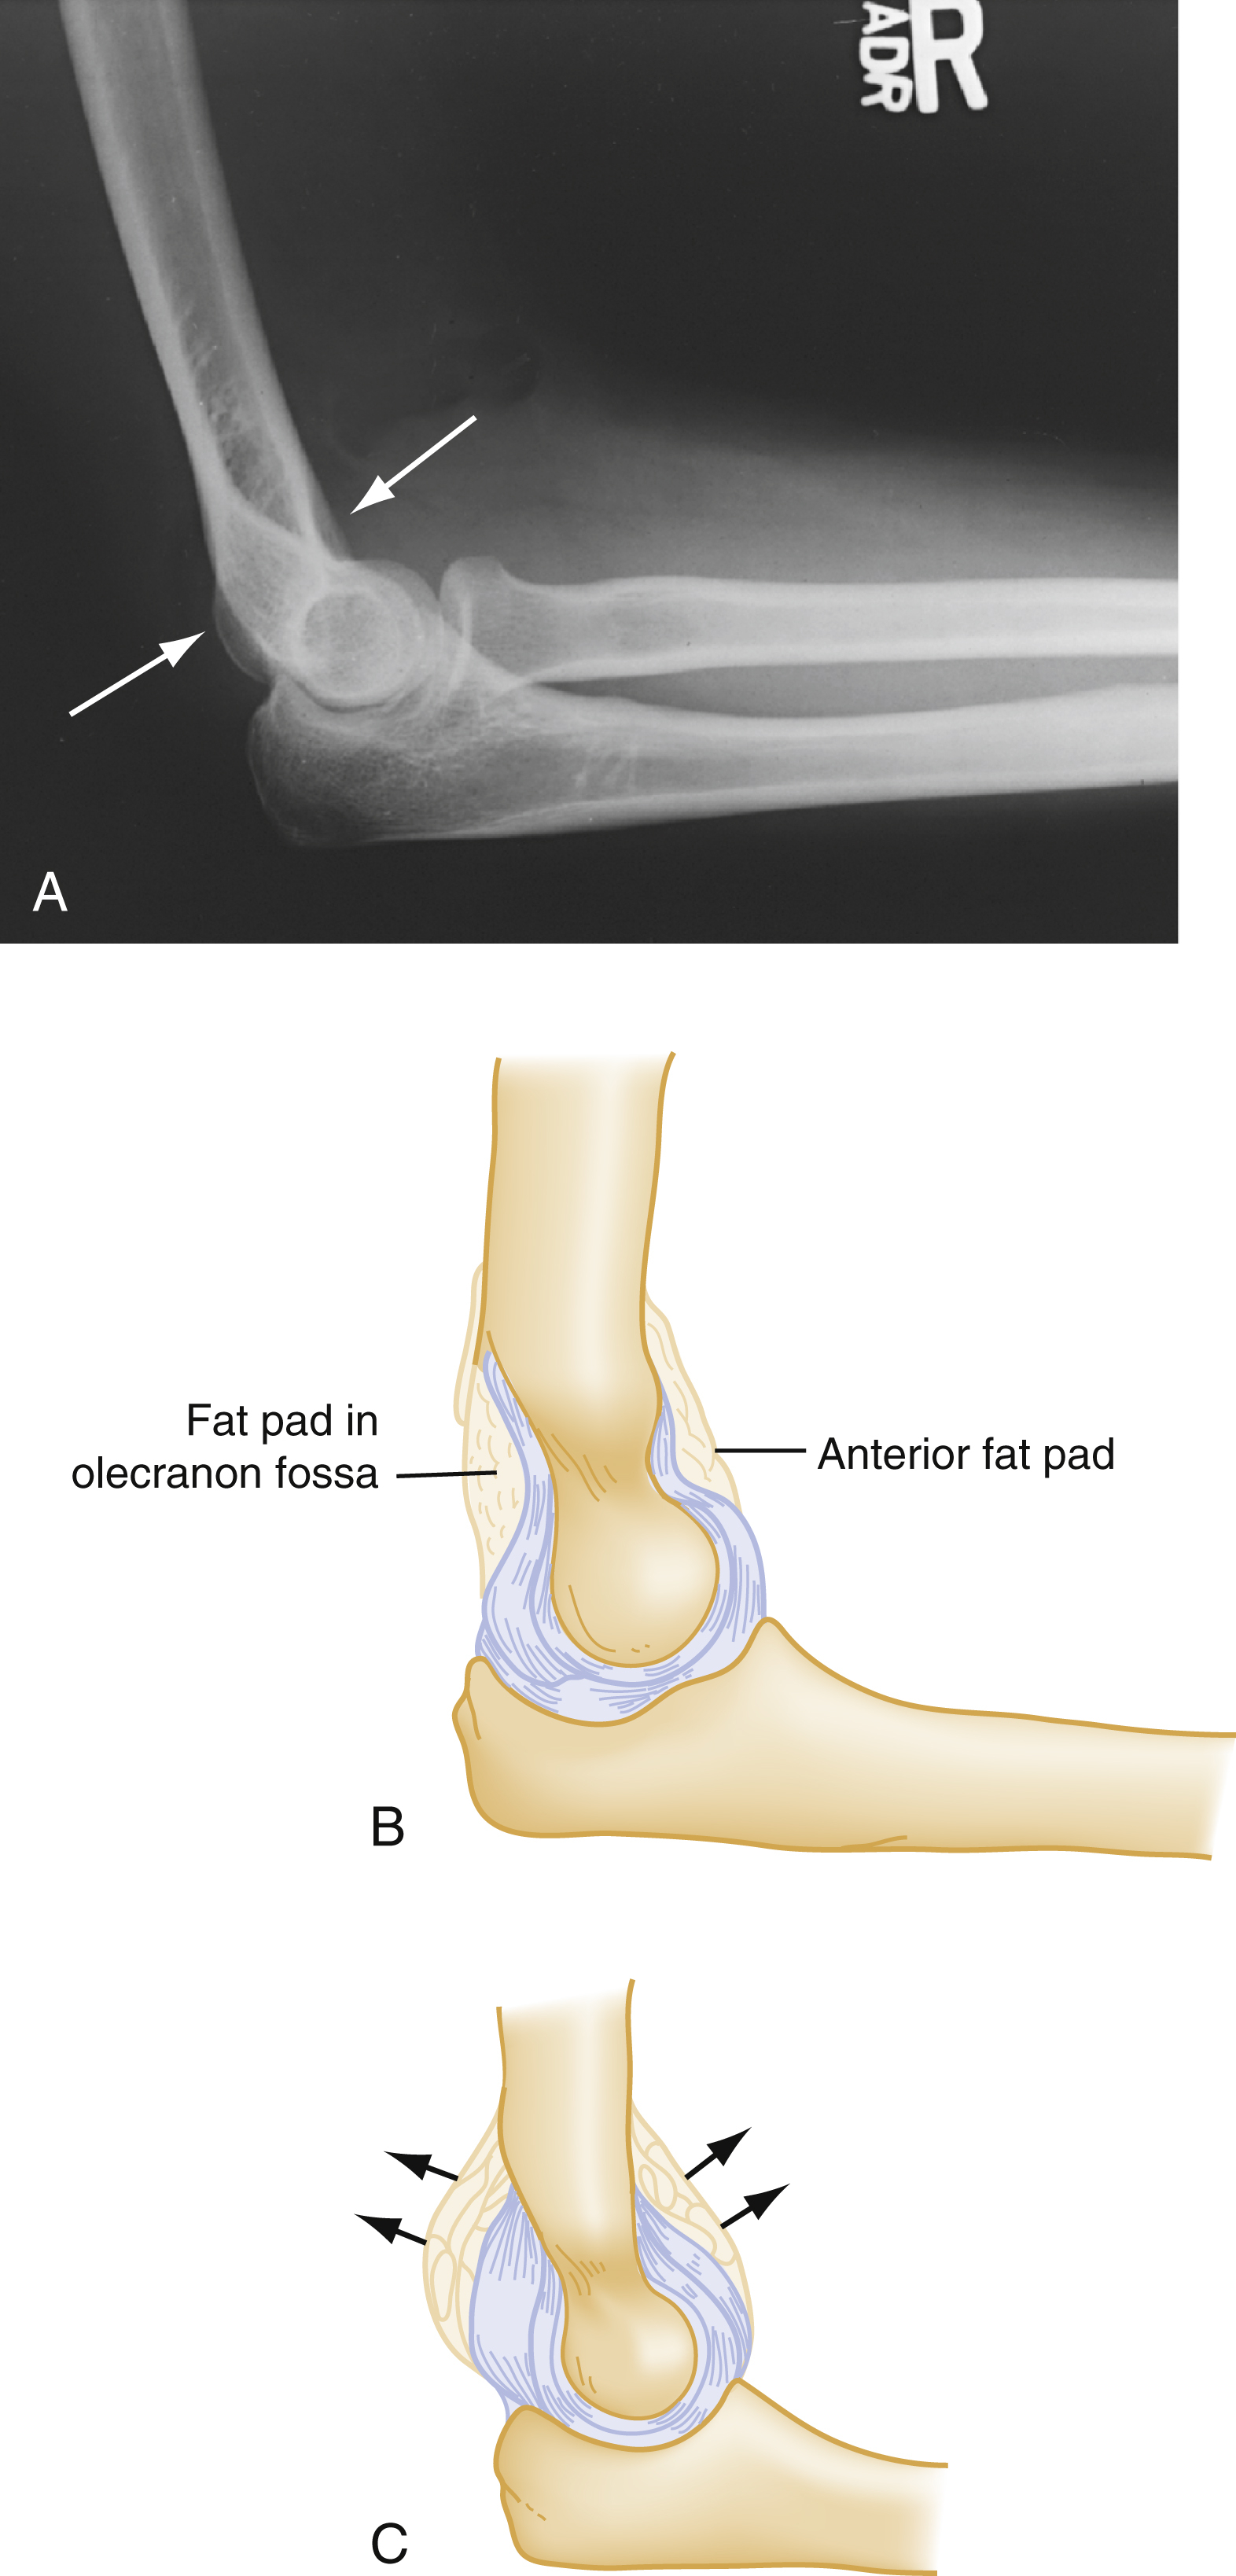

On lateral elbow x-ray, a small anterior fat pad, parallel to the anterior surface of the humerus, can be a normal finding. Any convex (“sail sign”) anterior fat pad and all posterior fat pads are pathological and indicate the presence of joint effusion.

In the setting of trauma, patients with a radiological posterior fat pad sign of the elbow are assumed to have an intra-articular skeletal injury. In adults, a posterior fat pad sign is indicative of a radial head fracture, whereas in children, a supracondylar fracture is more likely. In the absence of trauma, inflammation and infection also cause effusions with positive fat pad signs.

Examination begins with simple inspection and comparison with the contralateral limb. The position in which the extremity is held should be noted. Deformity may indicate fracture, dislocation, or hematoma. Range of motion may be evaluated, depending on the appearance of the extremity and suspicion of injury, but general manipulation of the acute injured extremity should be minimized. Bony prominences are palpated with notation of specific areas of tenderness. Crepitus, bony deformity, and pain in an acutely injured limb are virtually diagnostic of a fracture. The radial head specifically is palpated for tenderness. Intra-articular elbow fractures, including those of the radial head, are universally associated with effusion (hemarthrosis). Elbow effusions are notoriously difficult to discern on examination but are readily identified on lateral radiographs ( Fig. 44.5 ). The extremity should be inspected for swelling, compromised circulation, or any wound that may indicate an open fracture.

(A) Anterior and posterior fat pads on lateral study (arrows) . (B) The anterior fat pad is normally a thin radiolucent stripe; the posterior fat pad is not visible. (C) An effusion displaces both fat pads. This posterior fat pad is now visible.

Most fractures in the elbow region are identifiable on plain film, but radial head and subtle supracondylar fractures may be difficult to visualize. Radiographic examination of the elbow for the presence of fat pads secondary to traumatic effusion provides additional clues. The normal cortex of the radius is smooth and has a gentle continuous concave sweep. If consistent with history and physical findings, any disruption of this smooth arc is considered evidence of fracture. Abnormalities within the soft tissues on elbow films are particularly important and may be the only radiographic sign of a fracture. Normally, fat surrounding the proximal elbow joint is hidden in the concavity of the olecranon and coronoid fossae. The elbow normally has a narrow strip of lucency anteriorly, parallel to the anterior surface of the distal humerus (the anterior fat pad). The presence of a posterior fat pad is not considered a normal finding. Injuries that produce intra-articular hemorrhage cause distention of the synovium and displace the fat out of the fossa, making the posterior fat pad visible on lateral radiographic views. This intra-articular swelling displaces the anterior fat farther anteriorly, where it takes the shape of a main sail of a boat. Thus, this radiographic finding is commonly referred to as the “ sail sign .” Displacement of the posterior fat pad makes it visible on the lateral radiograph as a “posterior fat pad sign” (see Fig. 44.5 ). In the setting of trauma, more than 95% of patients with a posterior fat pad sign have an intra-articular skeletal injury. These soft tissue findings occur even with subtle fractures, and when present in the setting of trauma, an occult fracture should be suspected. In adults without an identifiable fracture on radiograph, fat pad signs most often indicate a radial head fracture, whereas in children a supracondylar fracture is the more likely. In the absence of trauma, the presence of a fat pad suggests other causes of effusion (e.g., inflammation or infection). Of note, the fat pad sign may be absent in fractures where the injury is severe enough to rupture the capsule.